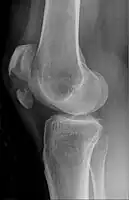

Bipartite patella

Some people have a normal bipartite patella or two-part patella which can appear as a fracture. The fragment is usually seen in the top outer corner of the patella and can be distinguished from a fracture by being present in both knees.[6]